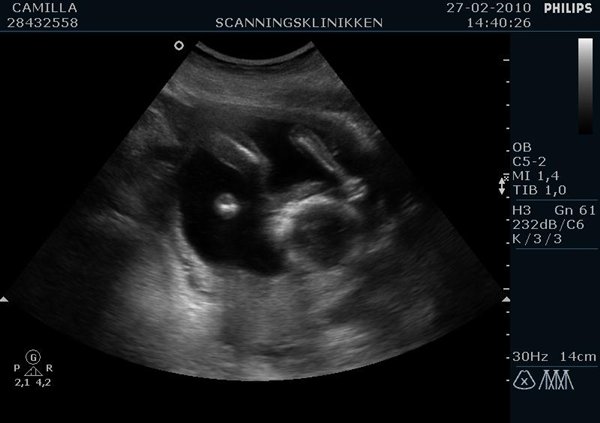

Ville lige ligge lidt billeder ind af min lille pige (Emilie?)  fra kønsscanningen igår

Vedhæftede fotos (klik for at se i fuld størrelse)

Billedet af hendes ædlere dele beviser 2stk skamlæber, (de to prikker)

Jordemoderen scannede mig fra alle leder og kanter og der var hverken tap eller pung at finde